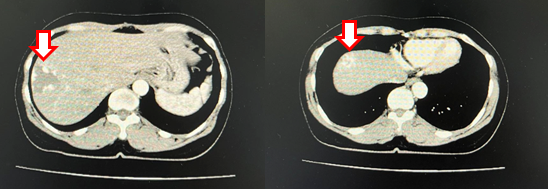

- Chụp cắt lớp vi tính ổ bụng:

Hình 1: Cắt lớp vi tính ổ bụng (09/06/22): Hình ảnh nhiều khối ngấm thuốc bàng quang (mũi tên) – Theo dõi u bàng quang đa ổ

Hình 2: Cắt lớp vi tính ổ bụng (09/06/22): Hình ảnh 2 khối u máu gan ở hạ phân thùy VII-VIII kích thước lần lượt là 35x38mm và 19x20mm (mũi tên)

- Cắt lớp vi tính ổ bụng:

Hình 6: Cắt lớp vi tính ổ bụng (16/06/23): không thấy các tổn thương thứ phát tại bàng quang (mũi tên)

Hình 7: Cắt lớp vi tính ổ bụng (16/06/23): Hình ảnh u máu gan phải, khối lớn nhất kích thước 35x38mm (không thay đổi đáng kể so với phim cũ 06/2022) (mũi tên)

Hình 8: Cắt lớp vi tính ổ bụng (06/03/24): Không thấy hình ảnh u cục, tổn thương thứ phát tại bàng quang (mũi tên)

Hình 9: Cắt lớp vi tính ổ bụng (06/03/24): Hình ảnh u máu gan phải, khối lớn nhất kich thước 36x52mm (mũi tên)